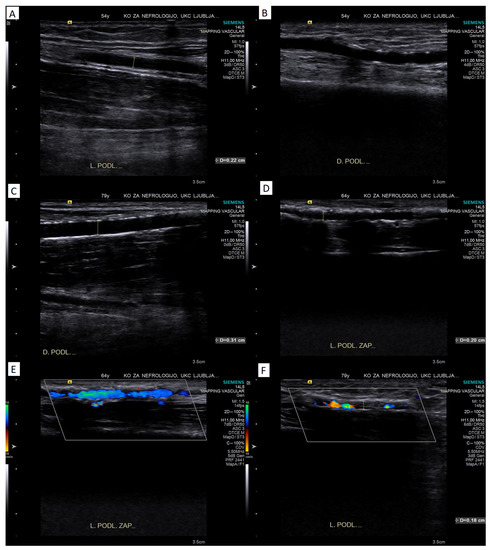

4.2.2. Pulsed-Wave Doppler Assessment

Peak Systolic Velocity

Doppler Curve Assessment, Acceleration Parameters

Reactive Hyperemia Test